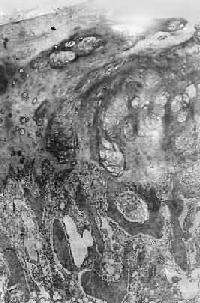

图17-8 骨肉瘤

多形性肉瘤细胞直接形成肿瘤性骨样组织